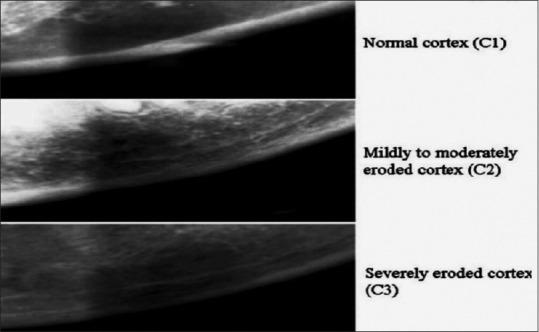

The present cross-sectional study included 80 subjects in whom mandibular cortical index (MCI), mandibular cortical width (MCW), panoramic mandibular index (PMI), alveolar bone loss (ABL), and bone height in 1 premolar (Hp) and 1 molar (Hm) were assessed to evaluate the alveolar bone loss.

The findings of the present study revealed a significant association between MCI and age for females with C2 and C3 categories being more common with advancing age. Also, a significant difference could be seen in relation to gender (p-value = 0.0315) for MCW with a concomitant decrease in values of MCW in females >60 years of age. The vertical bone height of the edentulous mandible at 1 premolar (Hp) (p-value = 0.0071) and 1 molar (Hm) (p-value = 0.0044) regions were also found to be more in males than females.

本研究结果显示,女性中MCI与年龄之间存在显著关联,C2和C3类别随着年龄增长更为常见。此外,MCW在性别方面存在显著差异(p值 = 0.0315),60岁以上女性的MCW值随之降低。还发现,无牙下颌1颗前磨牙(Hp)区域(p值 = 0.0071)和1颗磨牙(Hm)区域(p值 = 0.0044)的垂直骨高度男性高于女性。